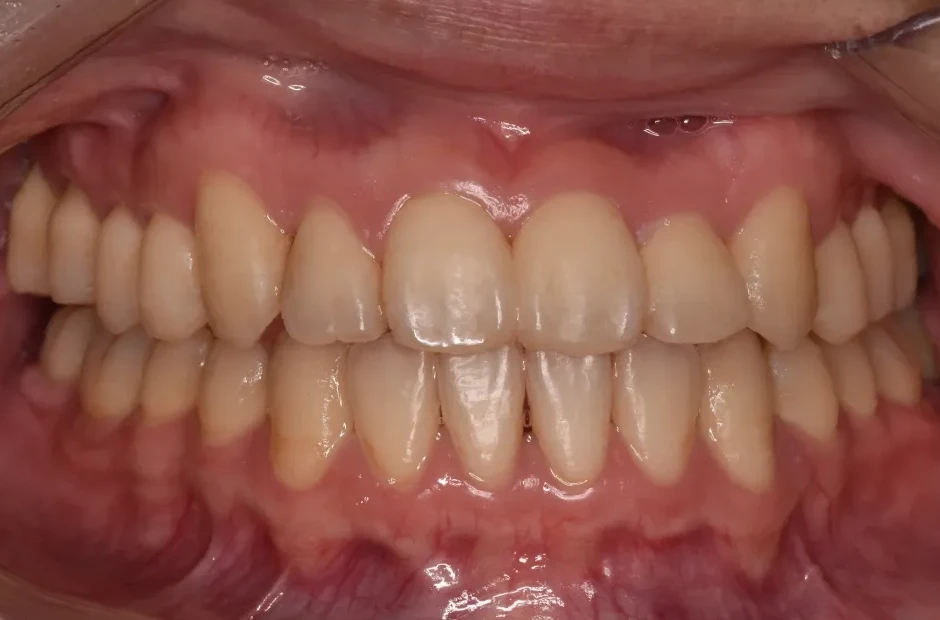

反対咬合

| 診断名・主訴 | 下顎前突、叢生 |

|---|---|

| 年齢・性別 | 23歳・女性 |

| 治療期間・回数 | 3年 |

| 治療に用いた主な装置 | 上顎5,5 下顎4,4 |

| 抜歯部位 | 舌側矯正 |

| 治療費 | 100万円(税抜) |

| リスク・副作用 | 装置による違和感・疼痛・歯肉退縮・歯根吸収・虫歯のリスクなど |

治療前

治療後